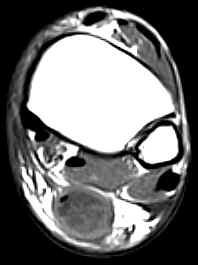

• Partial Rupture:

• There is  partial continuity of a portion of the tendon fibres on at least one sagittal section. There is no tendinous gap.

• The tendon may be thickened and usually exhibits focal areas of intermediate signal intensity on the T1W images and increased signal intensity on the T2W images due to edema and/or hemorrhage.

• It may be difficult to differentiate between tendinitis and partial tears as the two often coexist. In uncomplicated chronic tendinitis there is focal or diffuse thickening of the tendon without increased intrasubstance signal intensity.